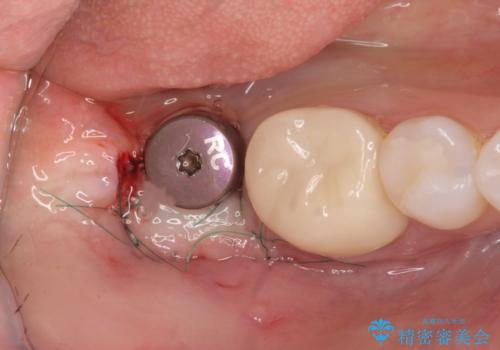

骨との結合する期間が早く、大きな咬合力にもしっかりと耐えることのできるストローマンインプラントを用いた咬合機能回復を計画します。

- 外科手術のため、術後に痛みや腫れ、違和感を伴います